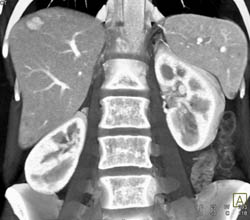

Cavernous Trnasformation of the Portal Vein With Portal Vein (PV) Occlusion